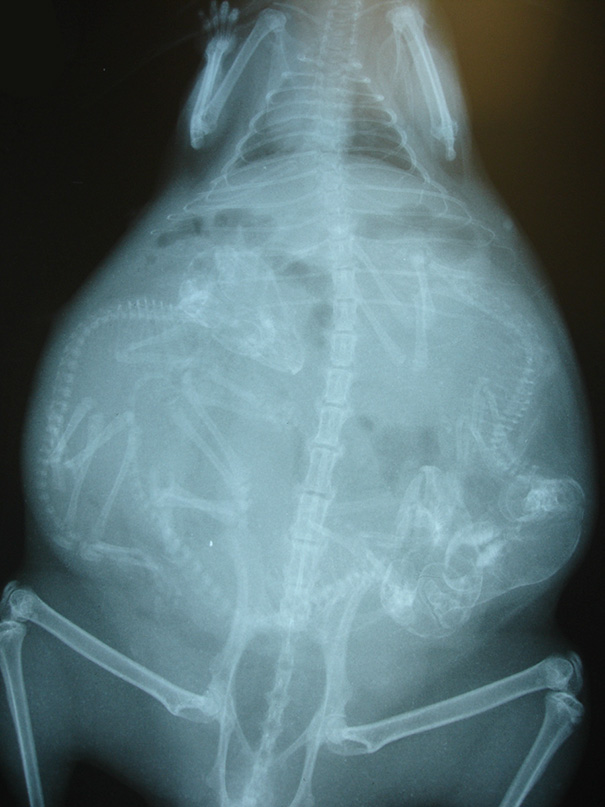

X-Ray Of Pregnant Bat

Why is it on one side. I'm not sure but it looks like it's bulging out the right not front.

This is normal. Any woman who has been pregnant can attest that sometimes the baby (or babies) will lay on one side. Can look pretty funny too! Have to remember there's also a lot of amniotic fluid around the baby which fills up the space so while it may look like the baby is smack in the middle it's often not.